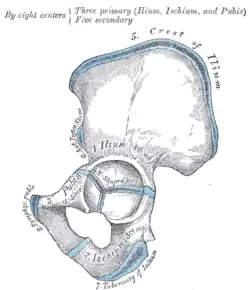

![]() Overview of Ilium as largest bone of the pelvis | |

The iliac crest is derived from endochondral bone.

-

Plan of ossification of the hip bone -